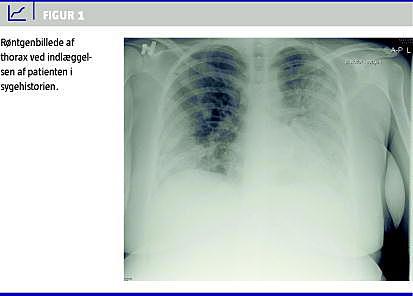

Ved indlæggelsen var hendes blodtryk 116/63 mmHg, pulsen 125 slag/minut, temperaturen 39,1 °C, respirationsfrekvensen 25 indåndinger/minut og iltmætningen 88%. Der var et leukocytniveau på 7,1 mia./l, og det C-reaktive protein-niveau var på 98 mg/l. En røntgenundersøgelse af thorax viste bilaterale pneumoniske infiltrater (Figur 1 ).